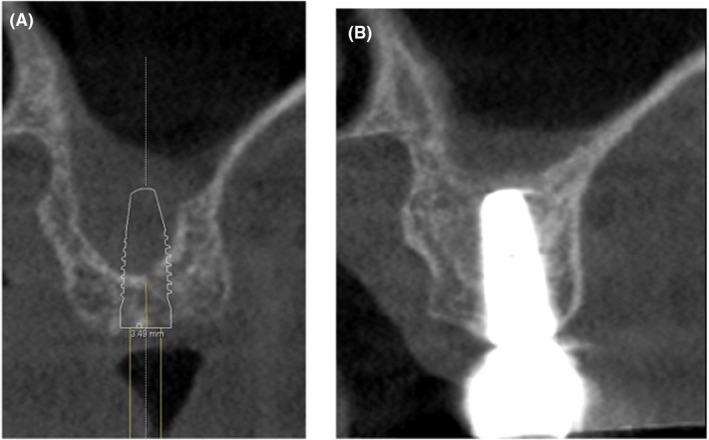

After tooth loss in the posterior area of the maxilla, sinus floor elevation is often required to compensate the vertical bone loss due to sinus pneumatization. This narrative review reports on the potential benefits of autologous platelet concentrates (APCs) during this procedure. As for transcrestal approach, APCs have been used as "sole" substitute/graft. However, because of the low number of clinical trials available with PRGF, and even none for PRP, no definitive conclusions can be made regarding their efficacy. The number of studies on the use of L-PRF were outnumbered indicating good feasibility for vertical bone gain, with a high implant survival rate and a low degree of complications. PRP and PRGF have not been studied as a "single/sole" substitute for a one-stage lateral window approach, probably because of the weak physical characteristics of the membranes. L-PRF alone appears to be a predictable grafting material for lateral maxillary sinus grafting and a reduced RBH should not be considered as a risk factor. Compared to a "standard" bone substitute L-PRF shows slightly less vertical bone gain (consider enough membrane application and use of bony window as new sinus floor roof over the implant apices), enhanced early resorption (first 6 months after application), but a similar stable bone gain afterward. For a two-stage lateral window approach, APCs "alone" cannot be recommended, due to their weak withstand to the sinus pneumatization forces. APCs combined with bone substitutes seem to accelerate bone formation, without any additional benefits on the long-term new bone gain. The use of L-PRF membranes for the treatment of perforations appears to be an effective treatment option, but further clinical studies are needed to confirm this. Even though the abovementioned statements are based on large numbers of studies, additional RCTs comparing APCs with different types of grafting procedures for sinus elevation are needed.